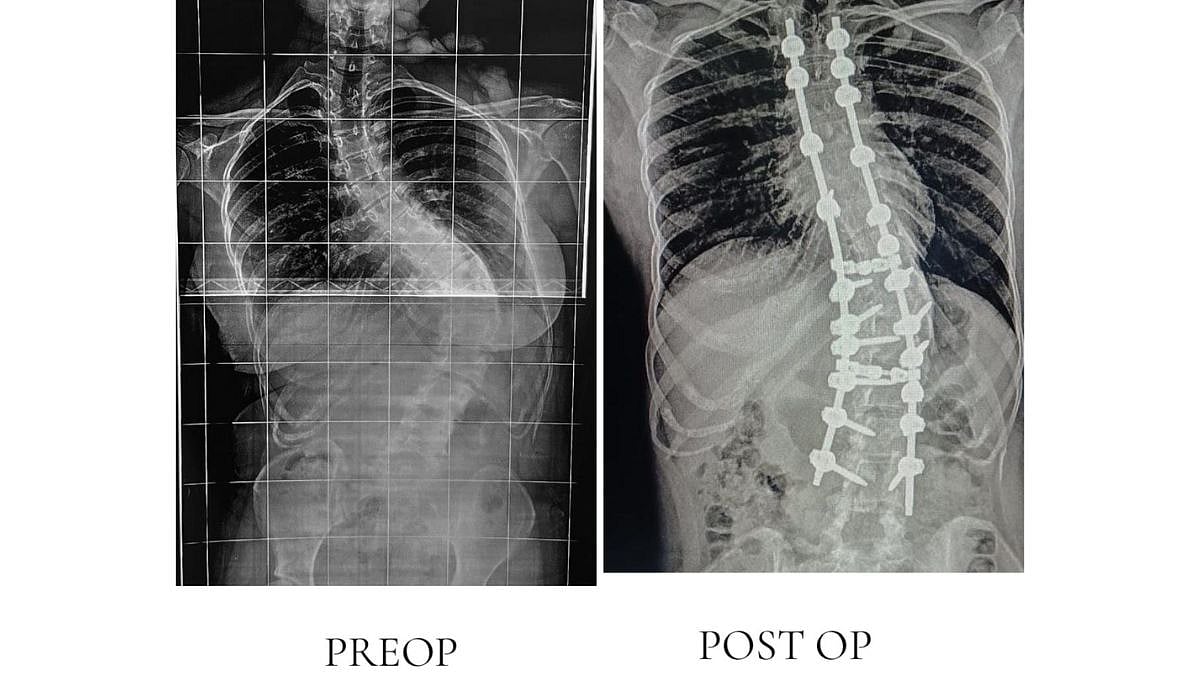

According to senior doctors, the patients — 24-year-old Divya Suryawanshi from Dhule and 15-year-old Master Rasul Shaikh from Nizamabad — had been living with progressive spinal kyphoscoliosis, a condition that severely impacts posture, mobility, and lung capacity.

For the first time in the state, surgeons used the cutting-edge Mazor X Spine Robot with O-arm navigation, which allows for highly accurate screw placement and real-time 3D imaging during surgery.

“The robotic system enables exceptional precision, reduces surgical risks, and facilitates faster recovery for patients with complex spinal deformities,” explained Dr Nadir Shah, Head of the Orthopaedics Department.